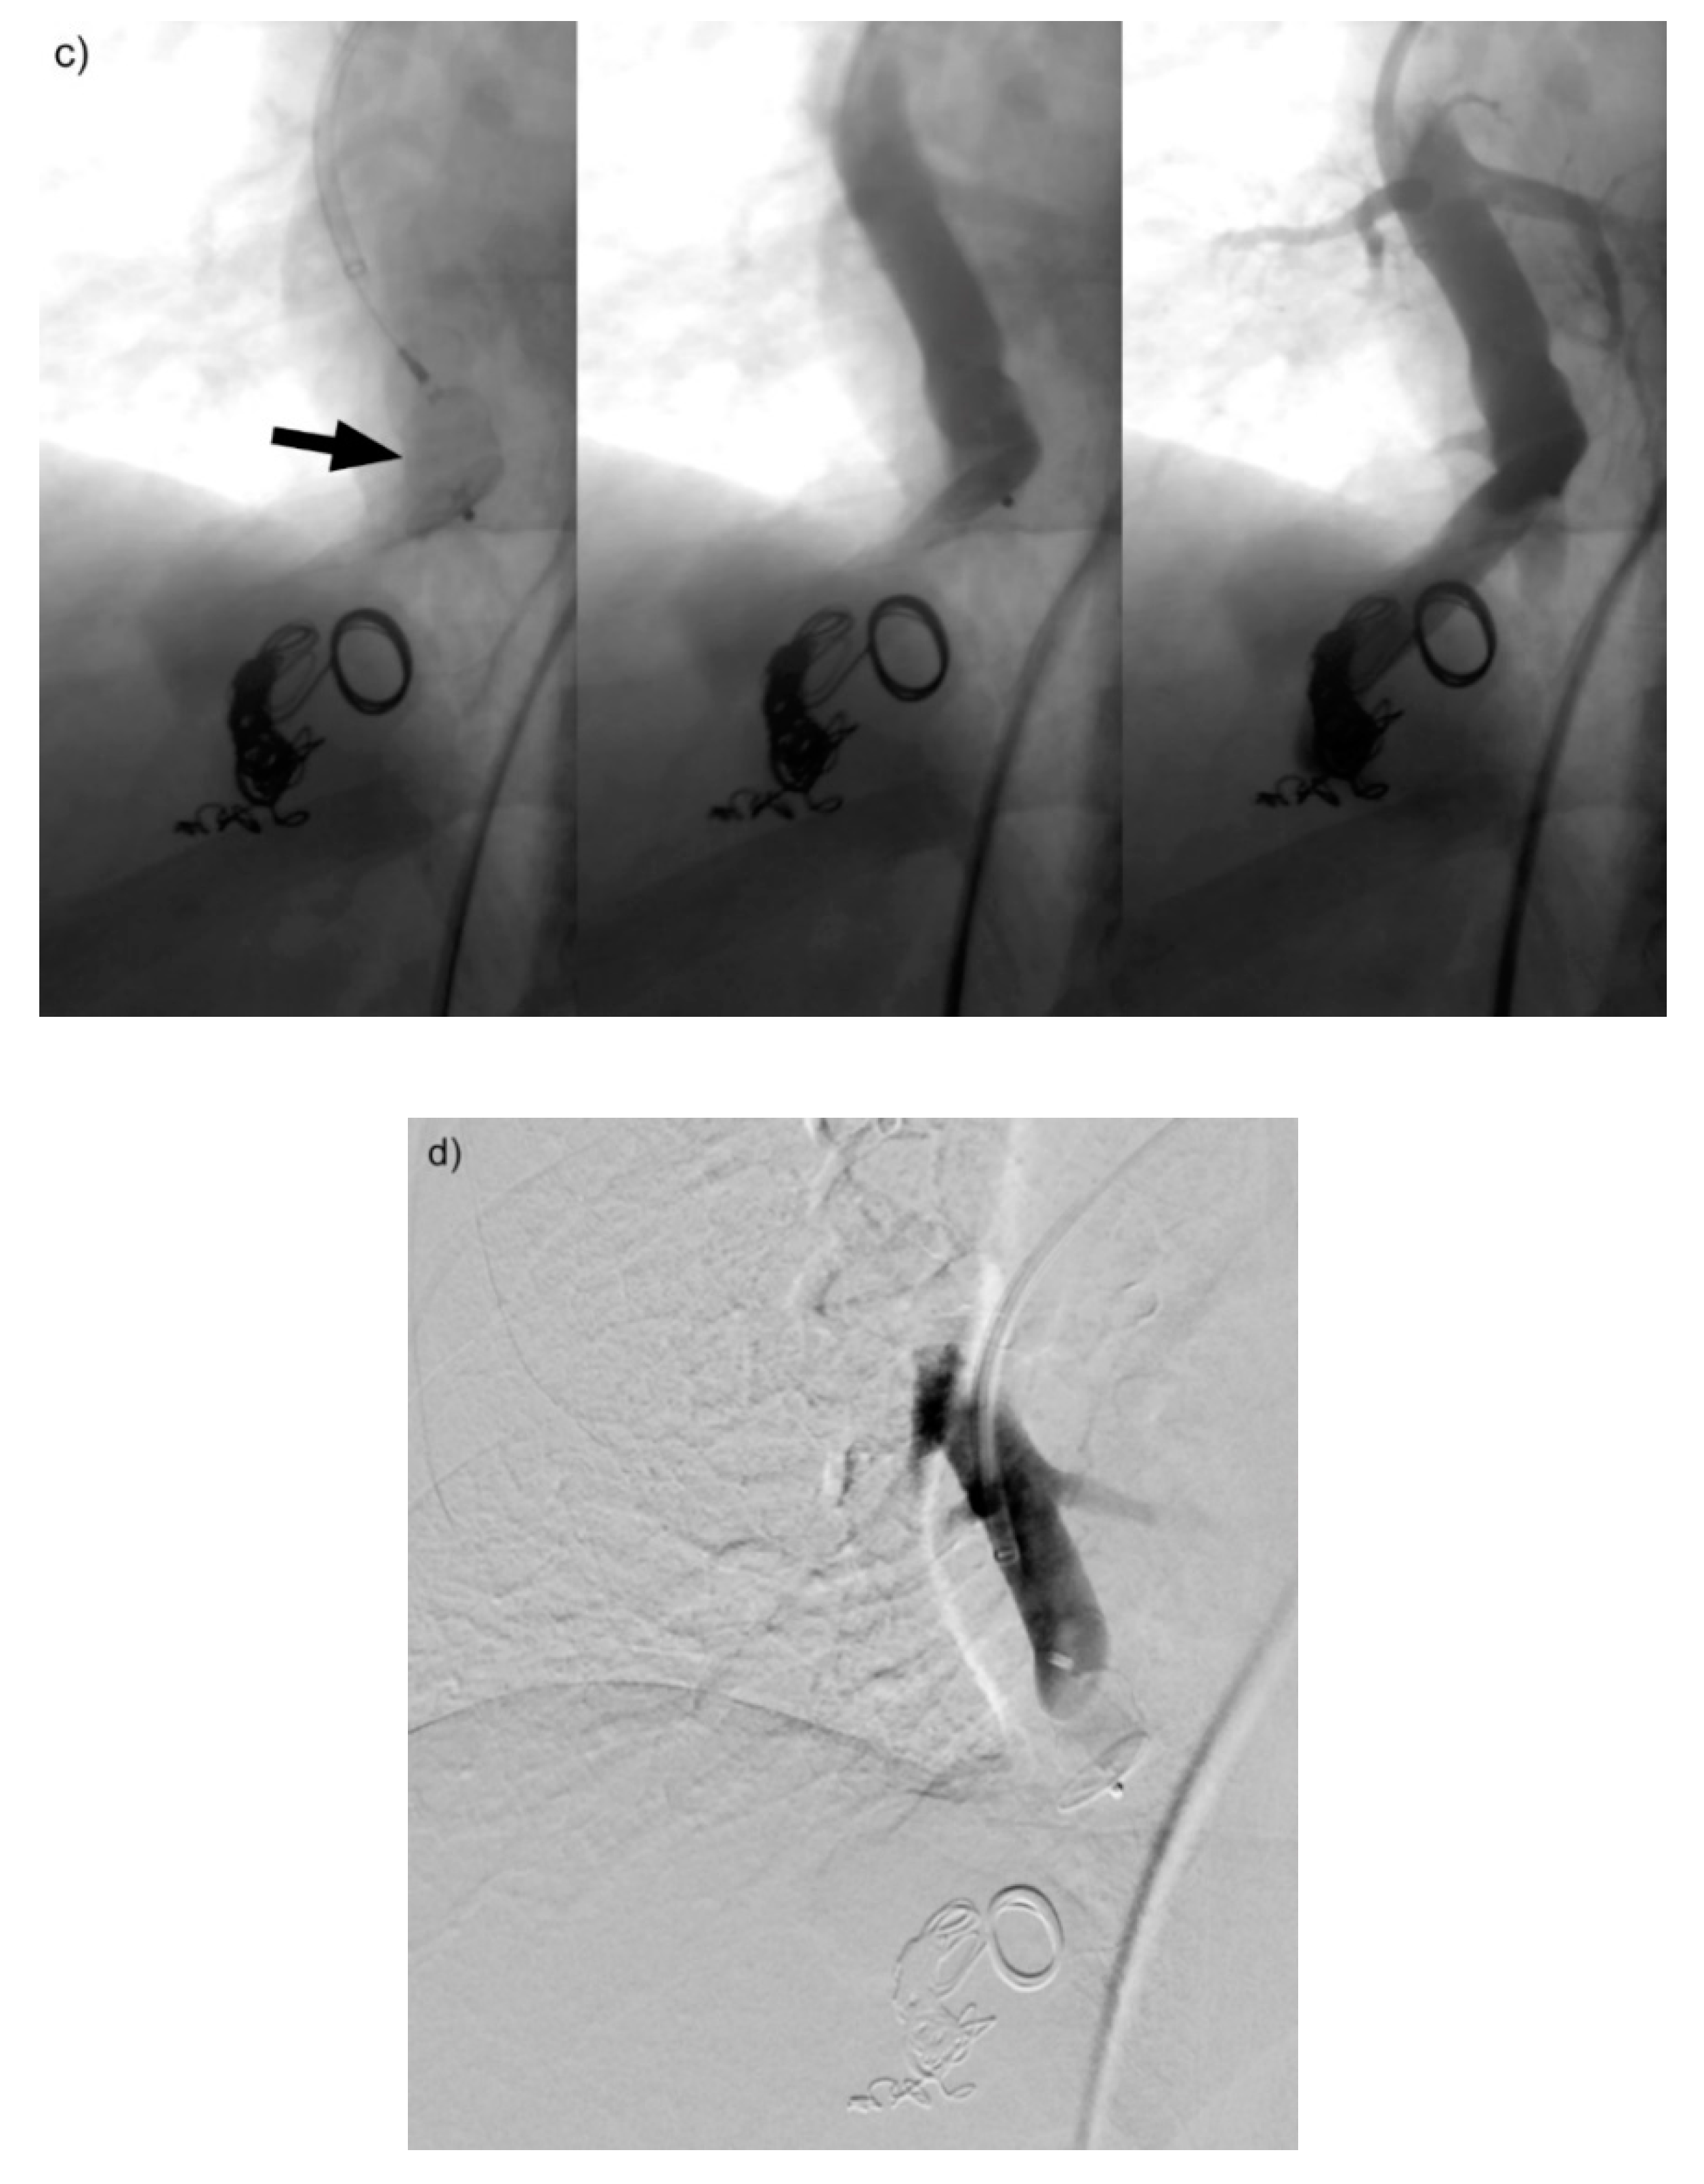

Figure 4. (ad) A giant re-perfused PAVM in the lower right lobe. In this case, pre-interventional DSA (a) shows two large feeding vessels originating from a common trunk, resulting in embolization being performed at the level of the bifurcation. With DSA performed just after implantation, (b) shows the amplatzer plug II still connected to the wire. Optimal positioning is depicted. The dynamic series in (c) shows the vascular plug (arrow) still penetrable to contrast medium, however, flow is already reduced. At 5 min post-implantation of the vascular plug (d), the feeding artery of the re-perfused PAVM is completely occluded.